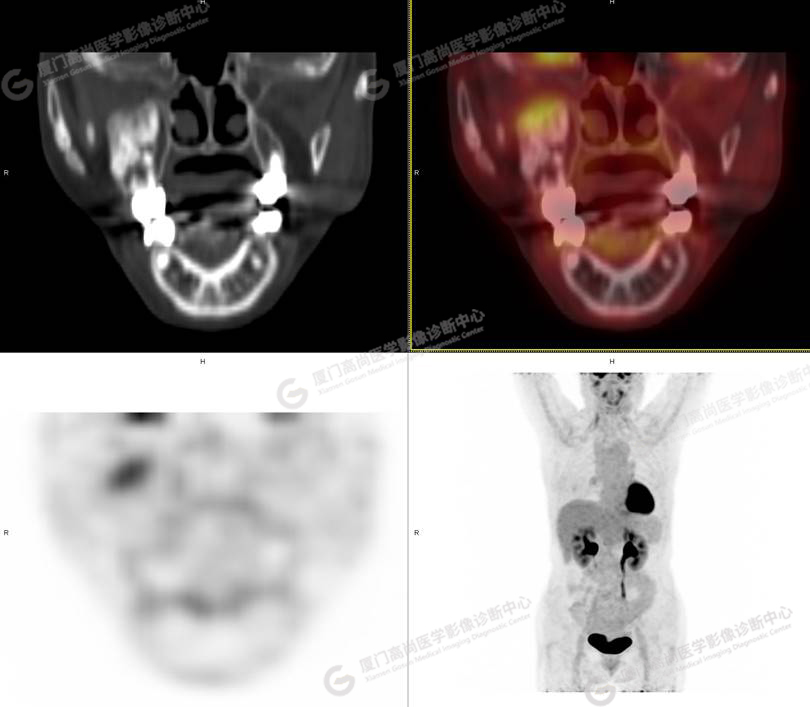

圖1

圖2

圖3

圖4

PET/CT所見:右側(cè)上頜骨、右側(cè)顴骨及右側(cè)額骨骨質(zhì)膨脹,其內(nèi)密度不均勻性增高,部分放射性攝取輕微增高,SUVmax 2.27。